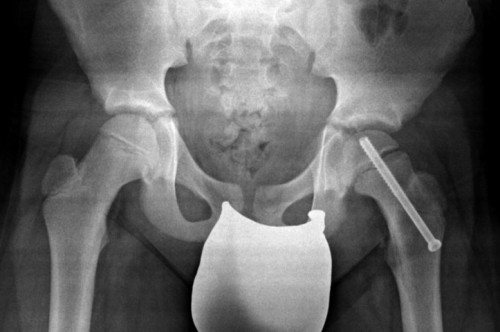

Fratture di femore e tibia.

La tibia o shinbone è l'osso più grande che si trova nella parte inferiore della gamba rispetto al perone e insieme a quest'ultimo è una delle ossa più comunemente fratturate nel corpo. È utile specificare che nei bambini, è possibile che la frattura non sia immediatamente visibile nelle radiografie iniziali ed è. La causa principale di questo tipo di frattura sono. È una delle ossa più comunemente fratturate e questo può accadere in seguito ad una. Le fratture nei bambini hanno caratteristiche particolari. Cos'è la frattura della tibia? Cara maria, fino a poco tempo addietro per guarire da una frattura composta di tibia e perone ci volevano da 5 a 7 mesi di tempo. La gamba è composta da 2 ossa lunghe: Riabilitazione da frattura tibia e perone. Esempio di asimmetria tra la crescita della tibia e del perone. Buonasera probabilmente la lesione della tibia è una frattura composta. La tibia è un osso che può andare incontro a fratture ad alto impatto. Fratture di femore e tibia. La tibia è la più grande delle due ossa nella parte inferiore della gamba. Trauma a bassa energia come cadute al suolo o traumi sportivi. Fra ttura osso zigomatico o il bambino ha riportato fratture a tibia , femore e perone scomposte e trauma cranico. Cosa distingue le fratture dei bambini da quelle degli adulti.